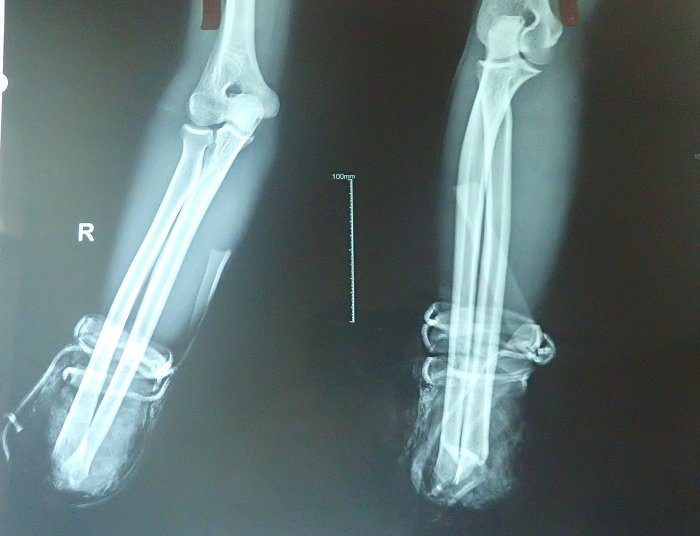

Phim chụp đoạn xương không có bàn tay phải.

Kíp mổ do bác sĩ Lê Minh Hoan, Trưởng khoa, mổ chính, cùng lúc sau nhiều giờ các bác sĩ phải nối xương, gân, cơ, dây thần kinh và các vi mạch…

Đến thời điểm này các bác sĩ nhận định, cơ bản bàn tay phải đã được nối thành công, ngón tay đã cử động nhẹ, thấy rõ màu hồng và nhiệt độ bàn tay ấm dần lên. Tuy nhiên, bệnh nhân sẽ còn phải được theo dõi, điều trị tích cực nhiều ngày sau nữa.